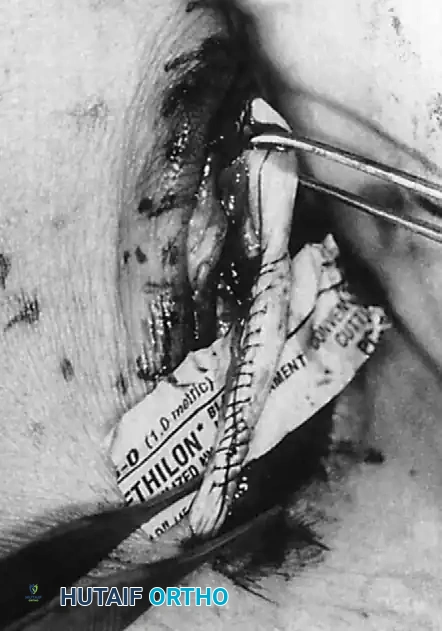

4. Tenosynovectomy and Tendon Debridement

Perform a complete tenosynovectomy, sharply debriding hypertrophic portions of the tendon sheath with a small rongeur or dissecting scissors. The findings at surgery represent a continuum: from clear fluid and relatively normal-appearing tendons, to small linear tears, to thickened, fibrotic sheaths encasing grayish, degenerative tendons.

Inspect the tendons meticulously for attritional, longitudinal fissuring. This pathology is most commonly located on the deep (anterior) surface of the peroneus brevis tendon, where it is compressed against the fibula by the overlying peroneus longus.

5. Tendon Repair Based on Tear Grade

For Grade I Tears (≤ 50% involvement):

If the tear involves less than 50% of the tendon's cross-sectional area, excise the smaller, degenerative section of the tendon completely. The remaining viable portion is then tubularized to restore a smooth gliding surface. This is achieved using a running 3-0 absorbable, braided suture, burying the knots to minimize friction.